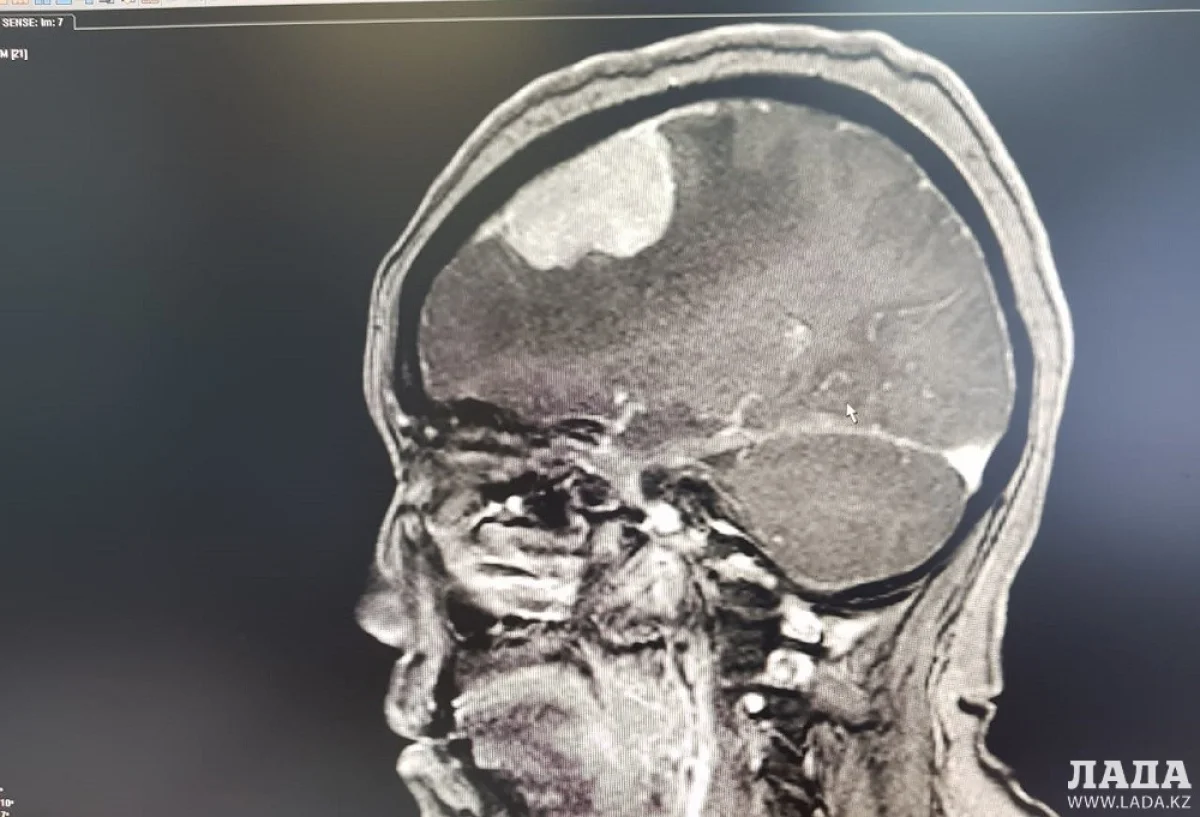

Опухоль мозга диаметром семь сантиметров удалили пенсионерке врачи Мангистау

Дополнительное обследование в аппарате компьютерной томографии (КТ) и магнитно-резонансной томографии (МРТ) показали у пенсионерки наличие отека правого полушария головного мозга.

- Врачи 28 февраля провели операцию по удалению опухоли в правой лобно-теменной области путем костно-пластической трепанации черепа пациентки. Операция прошла успешно, без осложнений, опухоль удалена полностью, - отметили в пресс-службе управления здравоохранения.